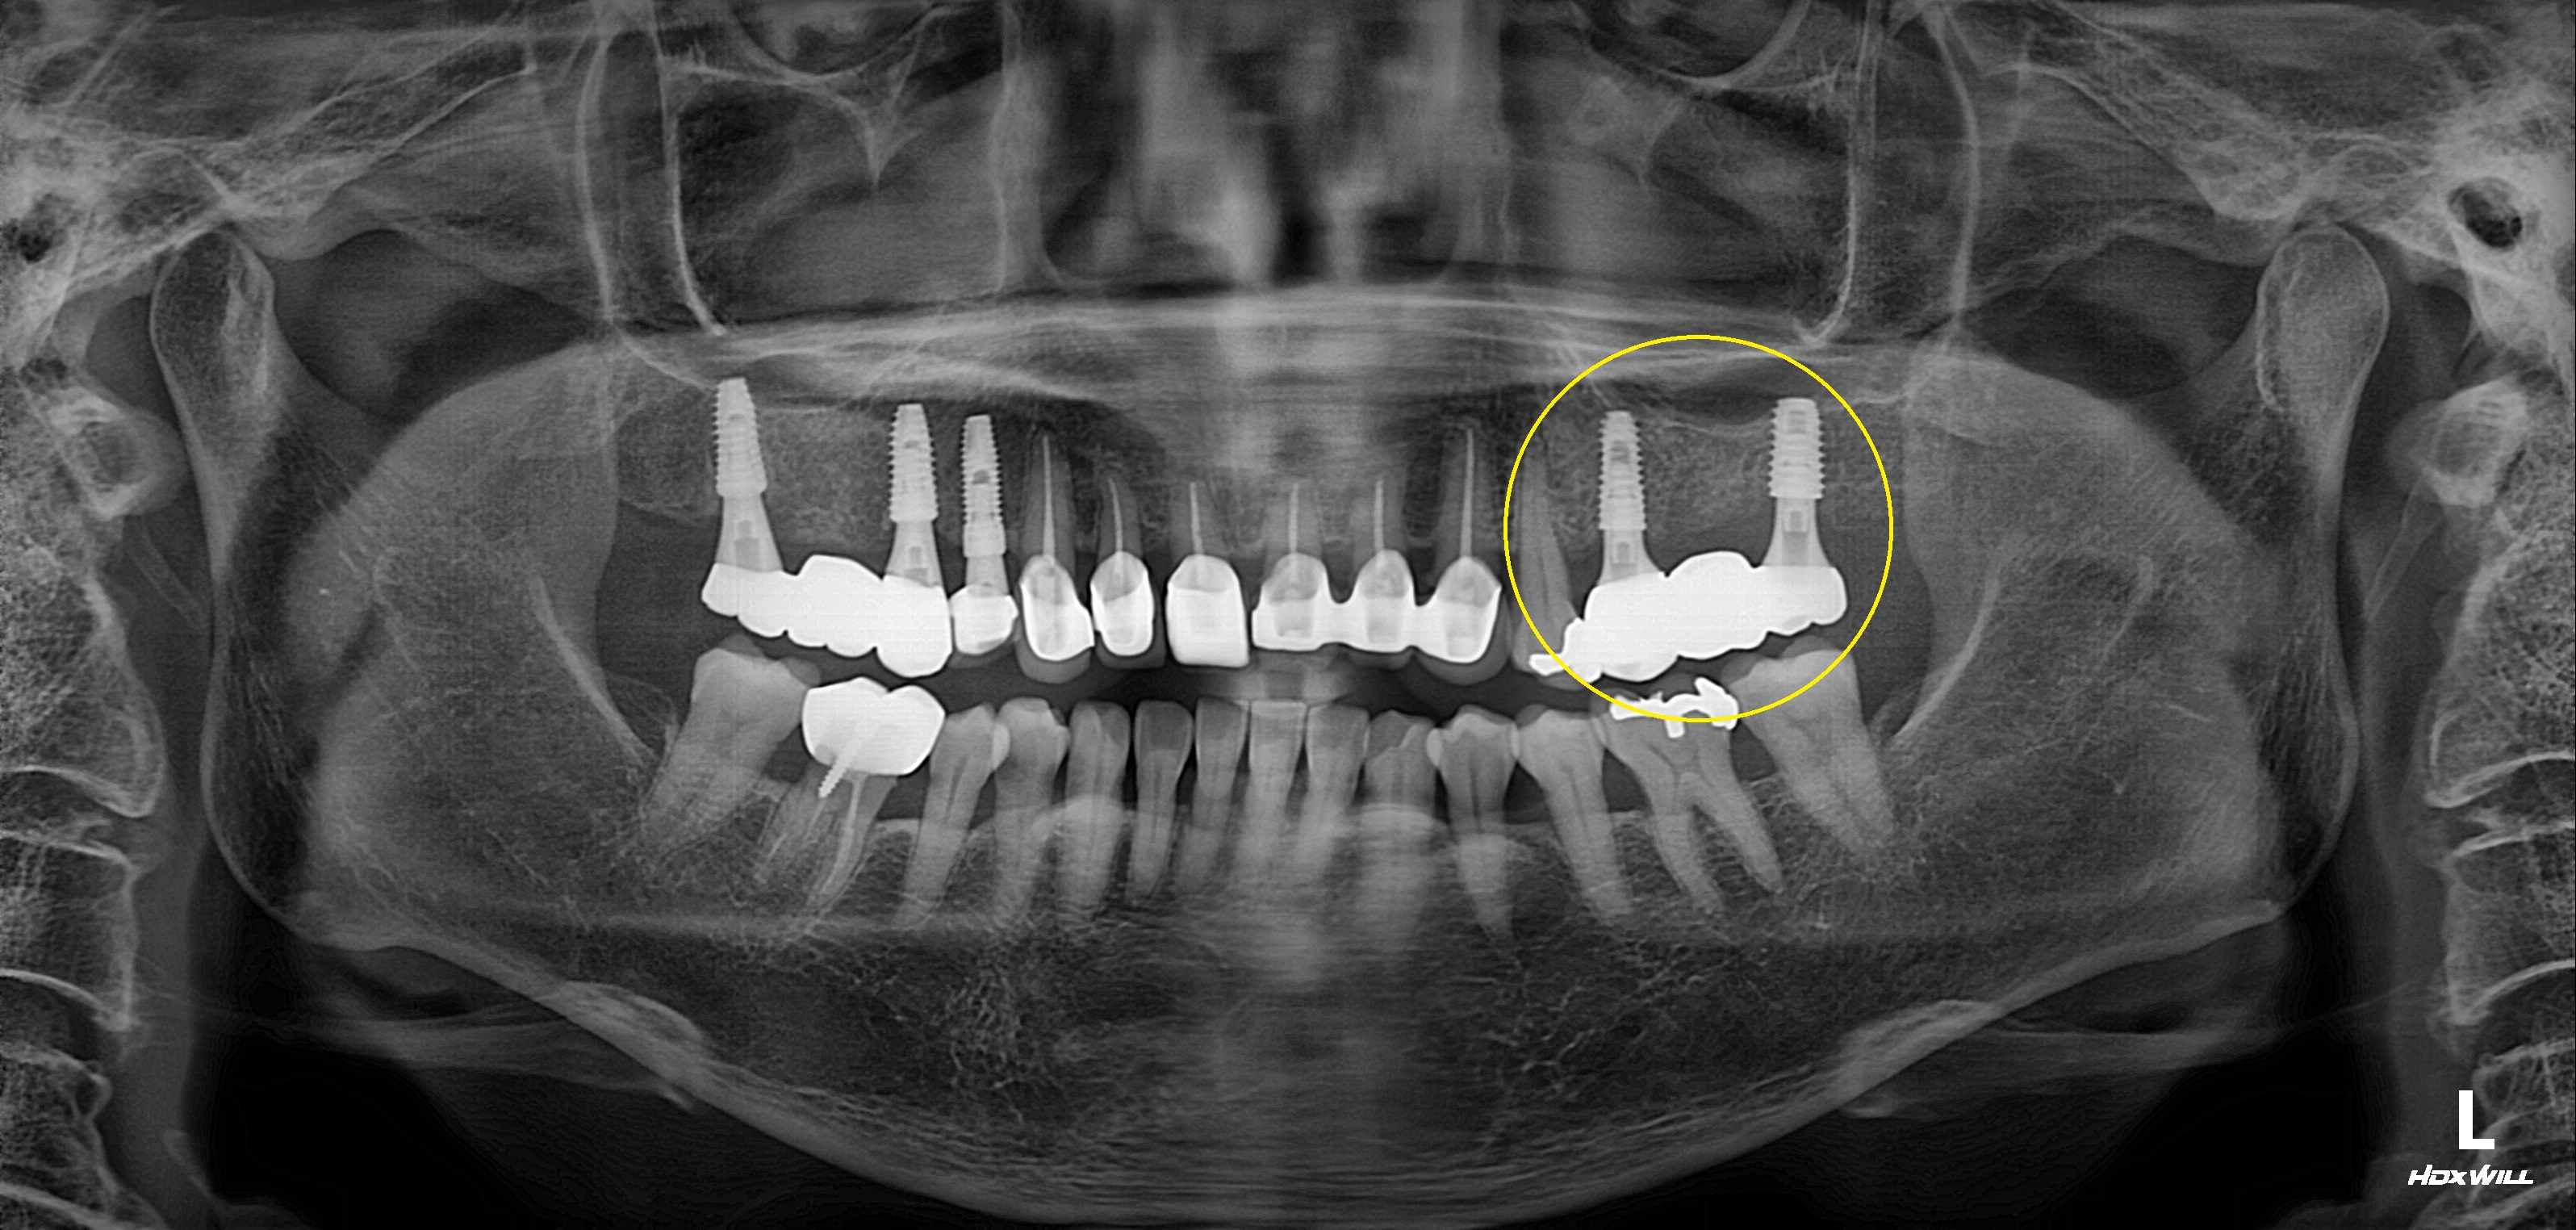

상악 구치부 임플란트 식립사례

전후사진

수술 전

수술 후